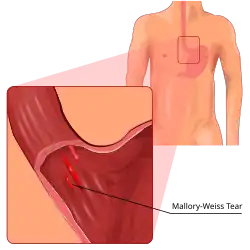

| Mallory–Weiss tear affecting the esophageal side of the gastroesophageal junction | |

Mallory–Weiss syndrome is a condition where high intra-abdominal pressures causes laceration and bleeding of the mucosa called Mallory-Weiss tears.[1] Additionally, Mallory–Weiss syndrome is one of the most common causes of acute upper gastrointestinal bleeding, counting of around 1-15% of all cases in adults and less than 5% in children. It has been found that tears are up to 2 to 4 times more prevalent in men than women. The tears can cause upper gastrointestinal bleeding and predominantly occur where the esophagus meets the stomach (gastroesophageal junction). However, the tears can happen anywhere from the middle of the esophagus to the cardia of the stomach. Mallory–Weiss syndrome is often caused by constant vomiting and retching from alcoholism or bulimia. Gastroesophageal reflux disease (GERD) is another risk factor that is often linked with Mallory–Weiss syndrome. However, not every individual with Mallory–Weiss syndrome will have these risk factors. Individuals with Mallory–Weiss syndrome will have hematemesis (vomiting up blood), however the symptoms can vary.[2]

The tear involves the mucosa and submucosa but not the muscular layer (contrast to Boerhaave syndrome which involves all the layers).[24] Most patients are between the ages of 30 and 50 years, although it has been reported in infants aged as young as 3 weeks, as well as in older people.[25][26] Hyperemesis gravidarum, which is severe morning sickness associated with vomiting and retching in pregnancy, is also a known cause of Mallory–Weiss tear.[27]